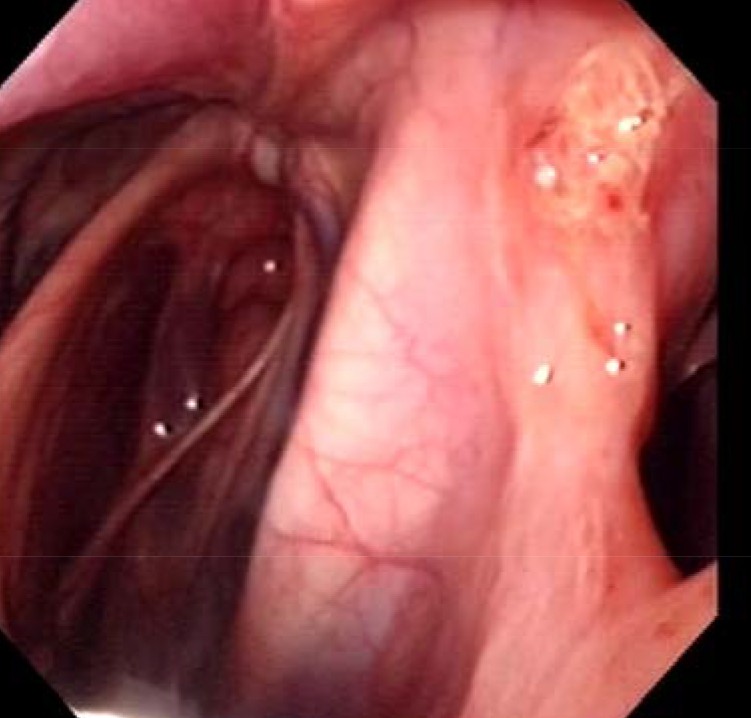

les photos des poches avant le curtage de 10j

Édité par kristine.19 le 21-04-2017 à 09h56

Merci pour l'illustration, ça donne un vraie idée de ce qui se passe

Ton endoscopie est vraiment très illustrative. Je vais essayer d'avoir celle de ma juju.

Nous ça donnait heureusement ça au niveau de la poche gauche (conduit de la plaque)

Photo de mauvaise qualité car prise depuis le telf.